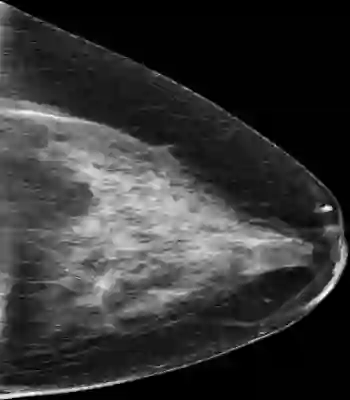

Mammography is used as a standard screening procedure for the potential patients of breast cancer. Over the past decade, it has been shown that deep learning techniques have succeeded in reaching near-human performance in a number of tasks, and its application in mammography is one of the topics that medical researchers most concentrate on. In this work, we propose an end-to-end Curriculum Learning (CL) strategy in task space for classifying the three categories of Full-Field Digital Mammography (FFDM), namely Malignant, Negative, and False recall. Specifically, our method treats this three-class classification as a "harder" task in terms of CL, and create an "easier" sub-task of classifying False recall against the combined group of Negative and Malignant. We introduce a loss scheduler to dynamically weight the contribution of the losses from the two tasks throughout the entire training process. We conduct experiments on an FFDM datasets of 1,709 images using 5-fold cross validation. The results show that our curriculum learning strategy can boost the performance for classifying the three categories of FFDM compared to the baseline strategies for model training.